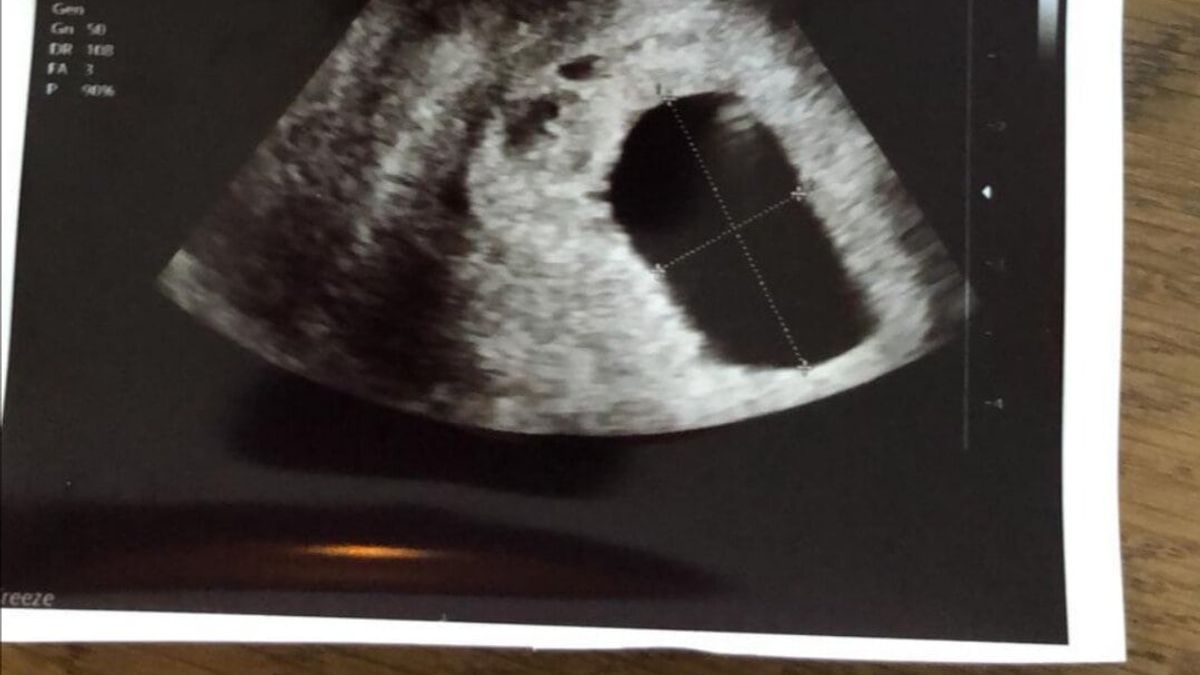

Ze bracht de inwendige echo naar binnen en ging kijken. “Aah kijk, een mooi vruchtzakje!” En toen bleef het stil…. Die secondes duurden voor mijn gevoel uren. “Ik zie nergens het “vruchtje”… Dat is gek”. Minder dan 7 weken kon ik nooit zwanger zijn, dus er moest toch echt wel iets te zien zijn. Ze besloot even te gaan zoeken. Helaas werd er niks gevonden. Ik mocht mij weer aankleden en zij vulde ondertussen dingen in op de computer. Toen ik weer plaats nam, bracht ze ons op de hoogte wat het vervolg kon zijn. Het zou een buitenbaarmoederlijke zwangerschap kunnen zijn of het vruchtje was al vroeg “gestorven” waardoor dit zou uitten tot een miskraam. Bizar, hoe je voorgevoel dit dan aangeeft.

Toen was het moment eindelijk daar, na 4 slopende uren reden wij weer samen naar het ziekenhuis toe. De echo werd gemaakt en gelijk werd er met zekerheid gezegd dat dit geen buitenbaarmoederlijke zwangerschap was. Dat was al fijn! Er werd afgesproken dat we voor de zekerheid één week zouden wachten tot een eventuele miskraam. Die week erna werden wij weer verwacht om dan alsnog een echo te maken of er toch niet alsnog een vruchtje zichtbaar zou zijn (ze gaven ons 1% kans), en anders zouden we dan overleggen of we de miskraam zouden opwekken met medicijnen of een curretage zouden doen.